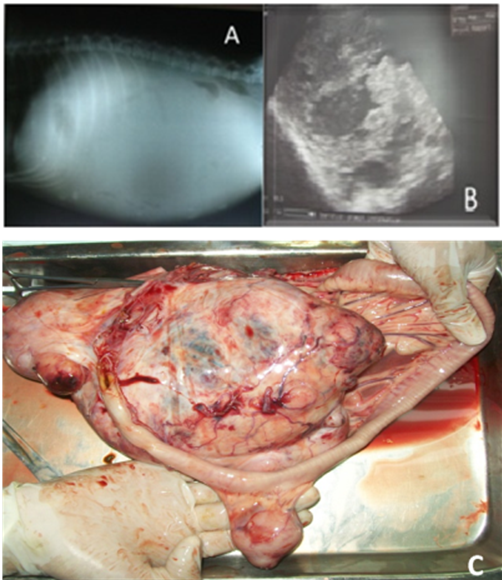

A side to side abdominal radiography was performed, showing widespread radiopacity and evidencing the presence of fluid in the abdomen (Figure 1A). By means of abdominal ultrasonography anechoic areas were observed in the abdominal mass (Figure 1B), suggestive of fluid content within the tumor, but the exam could not determine in which structure the mass was located. This way, an exploratory laparotomy was held, which revealed the mass location, attached to the small intestine mesentery. The patient died during the attempt to remove the mass owing to severe hemorrhage.

Figure 1 (A) X-ray, laterolateral view of the right abdomen. Radiodensity reveals fluid in the abdominal cavity. (B) Abdominal ultrasound. Anechoic areas show the presence of fluid within the tumor. (C) Macroscopic view of the tumor mass during necropsy.

Pathological findings. The canine was taken for necropsy. A tumor mass was removed and was firm with irregular surface. It measured about 18 cm long by 13 cm wide (Figure 1C). Lymph nodes were edematous. It was noticed great tumor vascularization, which had a bloody uncoagulated content. When cut the mass appeared to have irregular consistency.